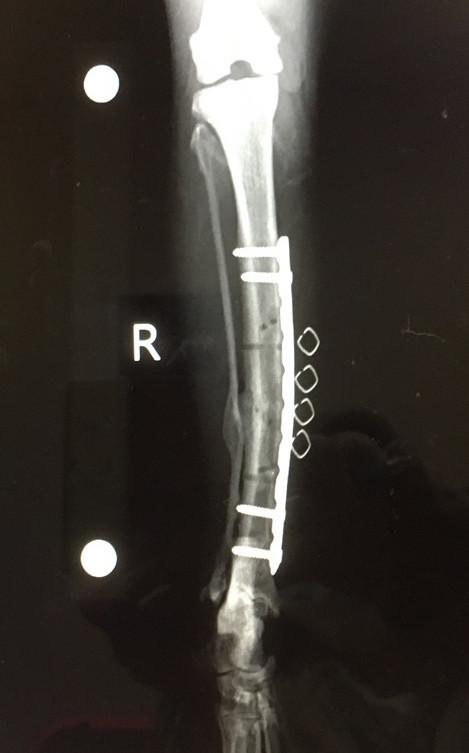

今回は補助プレートと内側2箇所のボルトを抜去しました。

骨形成が進んでいて、取るのが結構大変だったとのこと。

つーか今回の手術のレントゲンみて補助プレートにもボルトついてたのを知ったわ。

大小合わせて8本ボルト入ってたの?(^^;;;。

・・・そらー1回でとったら、再骨折のリスクありまくる危険。